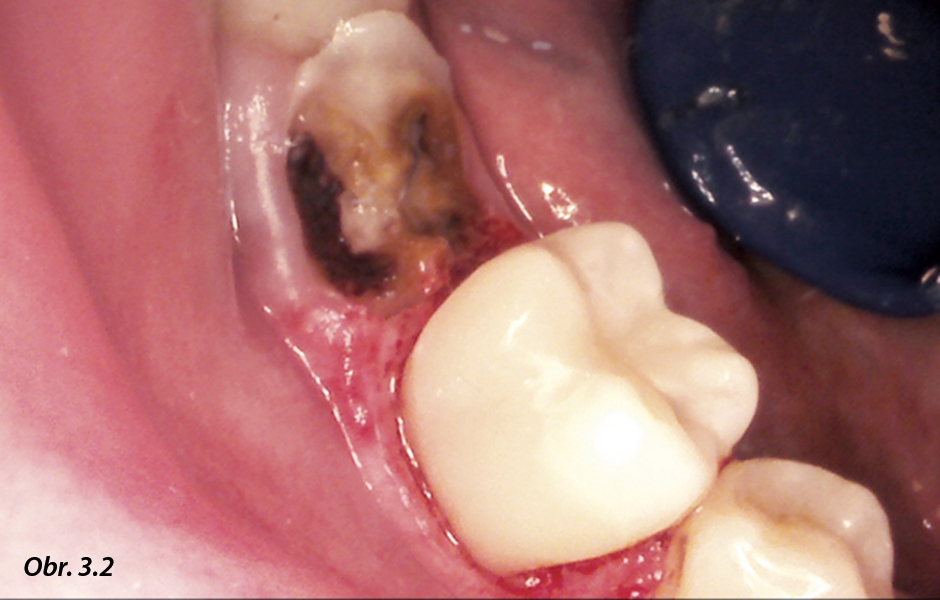

Stav po preparaci kazu dolního druhého moláru.

Gingivektomie provedena pomocí laseru.

Stav post op.